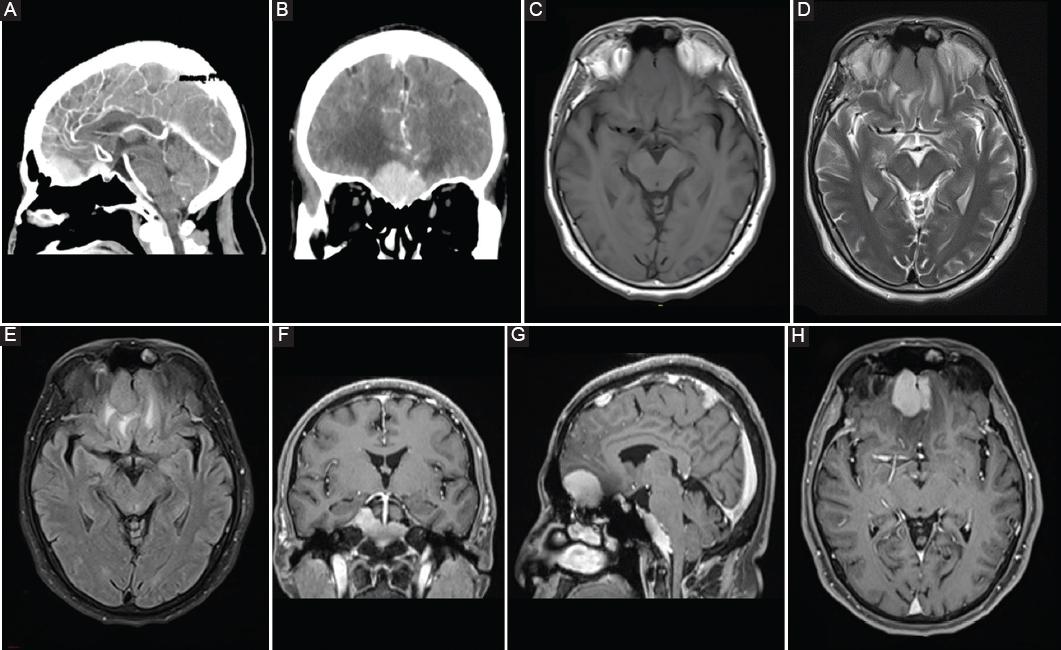

The neurological exam demonstrated preserved cognitive functions, hyposmia, and bitemporal hemianopsia despite normal visual acuity. Fundoscopy showed edema of the papilla in the left eye and slight pallor of the papilla in the right eye. The complementary lab tests were normal, the electroencephalogram reported abnormal bifrontal activity, and the computed campimetry corroborated both temporal fields’ affection. The computed tomography (CT)-scan reported three lesions: (1) midline in the floor of the anterior fossa in the crista Galli and cribriform plate (2) in the sphenoidal plane with extension to the tuberculum sellae, and (3) on the middle and lower portion of clivus. The three lesions presented the same characteristics; they were isodense with homogeneous and intense contrast enhancement. Magnetic resonance imaging (MRI) revealed isointense lesions with peritumoral edema in T1, T2, and fluid attenuation inversion recovery (FLAIR), with intense and homogeneous gadolinium-enhancement demonstrating a dural attachment (Fig. 1).

Figure 1 Neuroimaging studies. Enhanced sagittal head computed tomography-scan with an olfactory groove, tuberculum sellae, and clival lesion in (A) sagittal and (B) coronal sections (arrows). Olfactory groove lesion was isointense on magnetic resonance imaging in the (C) T1-weighted, (D) T2-weighted, and (E) fluid attenuation inversion recovery, demonstrated peritumoral edema. Homogeneous gadolinium-enhancement is shown in the (F) coronal, (G) sagittal, (H) and axial sections (arrows). Dural attachment was visible in the three lesions.

In the review of the radiologic findings, CT shows iso or hyperdense lesions with homogeneous contrast enhancement and vasogenic edema around the tumor and may even show bone erosion9. MRI usually shows extra-axial, dural based, and well-circumscribed, it is usually isointense in T1, iso, or hypointense in T2 with edema surrounding the tumor and homogeneous contrast-enhancement3,9. In a review of 10 cases, a dural tail was found in all cases, so RDD is also a differential diagnosis of meningiomas13. In this review, Zhu et al. concluded that unlike meningiomas, a typical hypointensity non-related to calcification on T2-weighted or FLAIR images could suggest the RDD diagnosis13. Despite MRI enhancement, in angiography, they are avascular lesions8. In our case, the imaging findings were similar to that reported, and a dural tail was identified in the three lesions, so the preoperative diagnosis coincided with the clinic of multiple meningiomas.